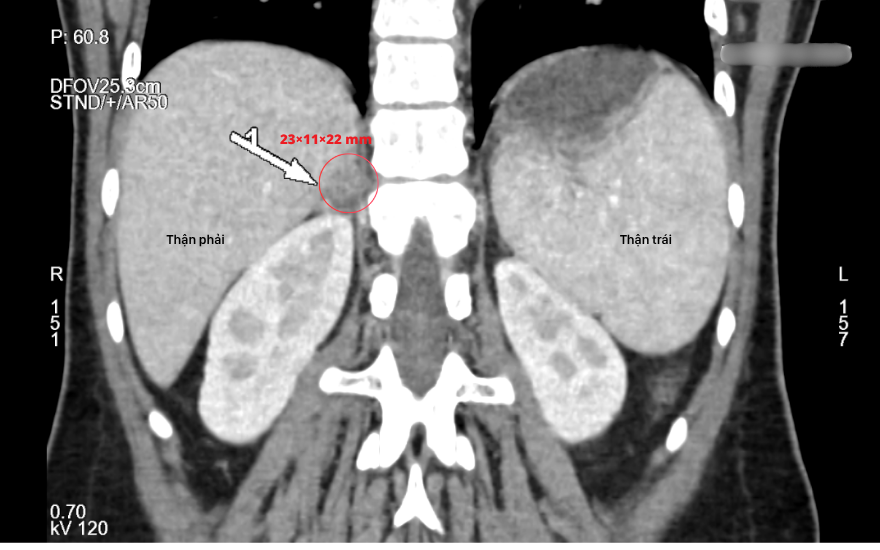

Tiếp theo, bệnh nhân được chụp CT ổ bụng để xác định vị trí tổn thương. Hình ảnh cho thấy một khối u kích thước khoảng 23 × 11 × 22 mm tại tuyến thượng thận phải, có đặc điểm điển hình của u tuyến lành tính. Từ toàn bộ các kết quả trên, bác sĩ chẩn đoán bệnh nhân mắc Hội chứng Conn do u tuyến thượng thận phải.

Hình ảnh CT cho thấy một khối u kích thước khoảng 23 × 11 × 22 mm tại tuyến thượng thận phải